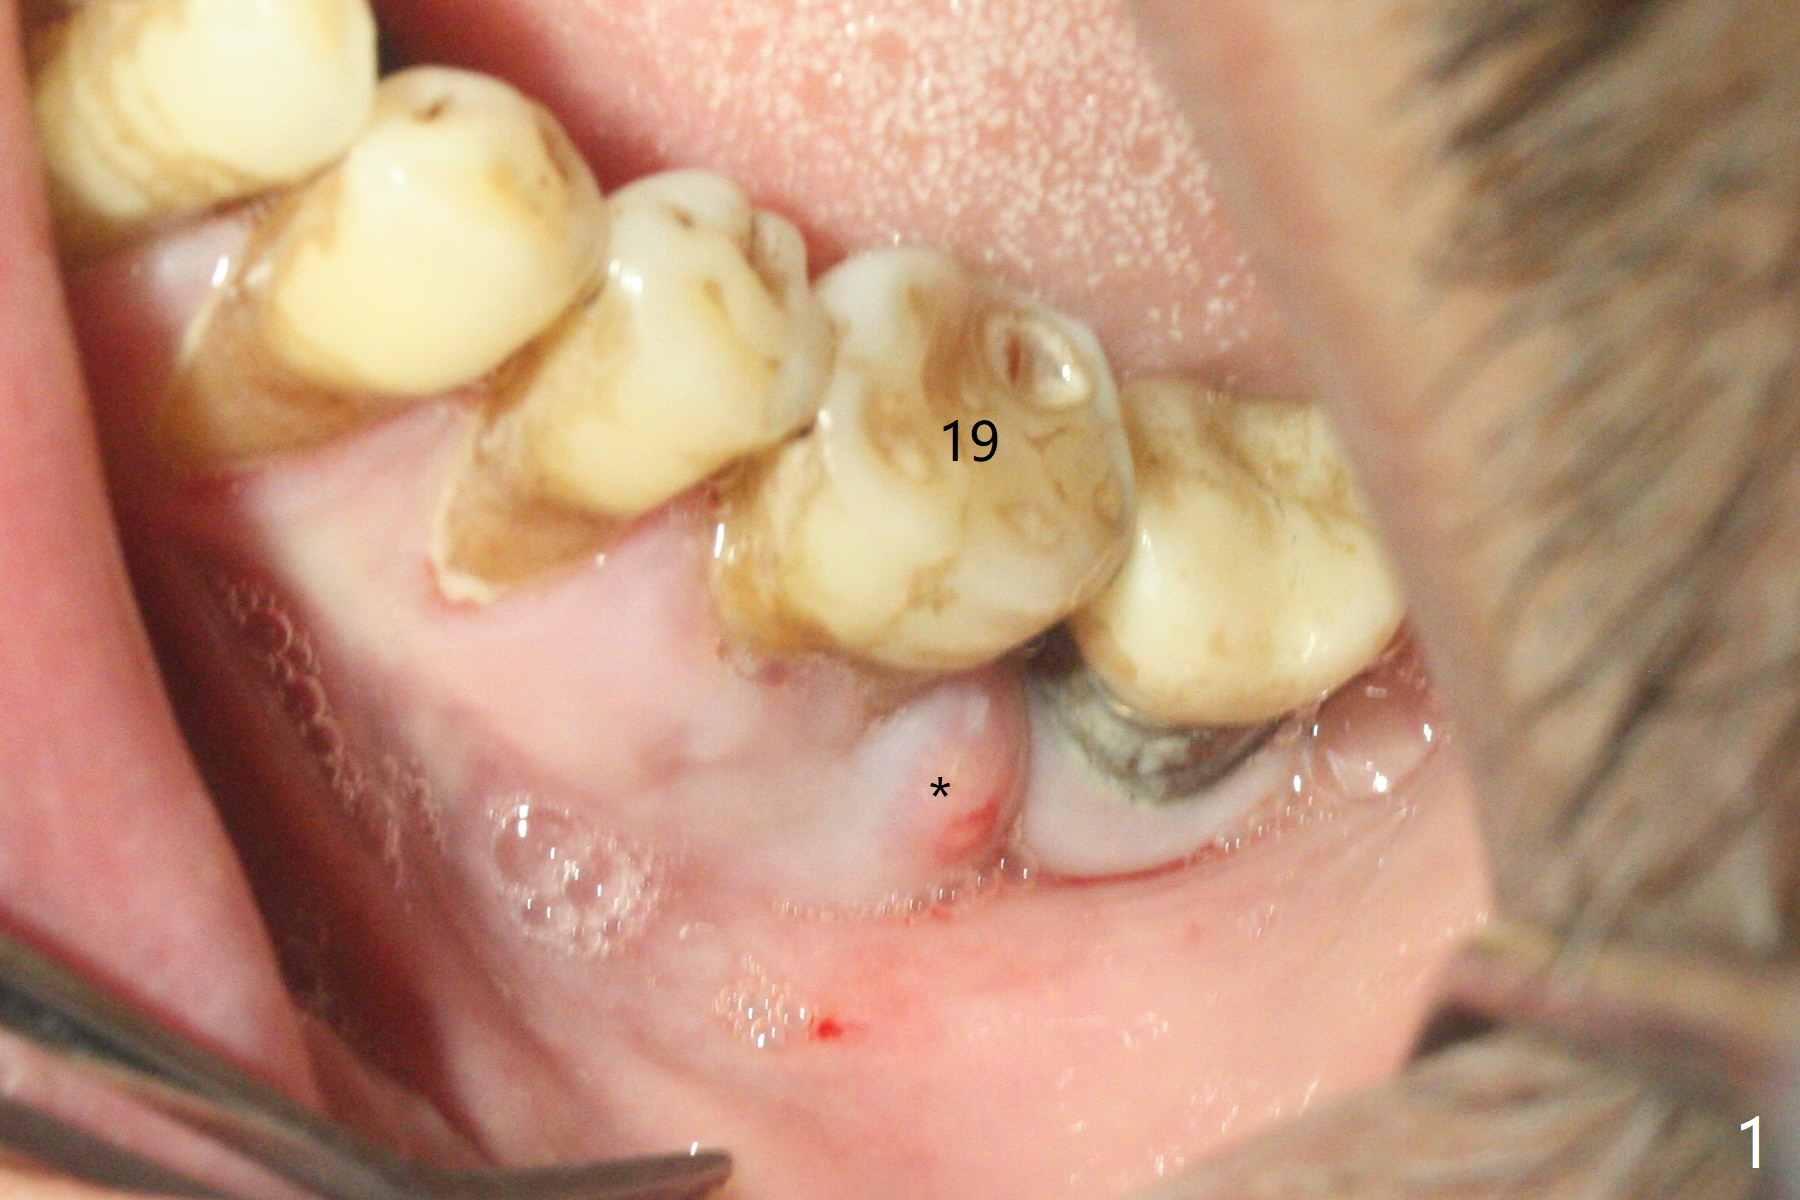

The 59-year-old man has so severe pain associated with #19 that he returns for extraction 2 days prior to guide arrival (Fig.1,2).拔牙后两天瘘道消失,牙槽窝口关闭(图三)。导板钻洞(4x7.3毫米)后,置入4x11毫米软组织水平植体,好像太短(图四),离神经(红虚线)3.5毫米。使用3.5x8.5毫米钻头后,植入4.5x9毫米骨水平植体,多次倒退,扭力35Ncm;马上安置基台(图五),然后粘性骨粉(图六:*)。